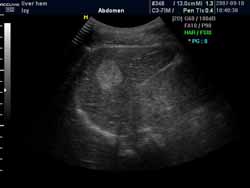

(血管瘤超聲表現(xiàn)可見高回聲血管團影)

(超聲穿刺針直接對瘤體進行注射治療)